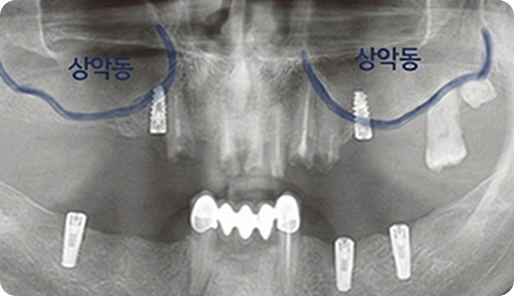

상악동이란?

위턱 뼈 속의 빈 공간을 말합니다.

상악동은 치아를 발치한 후 오랜 시간이 지나면 점점 밑으로 내려옵니다.

위턱뼈 상부에 비어있는 공간으로 동굴과 같다 하여, 상악동이라 합니다.

임플란트를 지지할 뼈가 없는 공간으로 얇은 막을 거상하고 공간에 뼈를 이식하여

임플란트를 식립하는 고난도 수술이 필요합니다.

상악동은 찢어지기 쉽고, 다른 질환을 유발할 가능성이 있어 섬세한 기술이 요구됩니다.